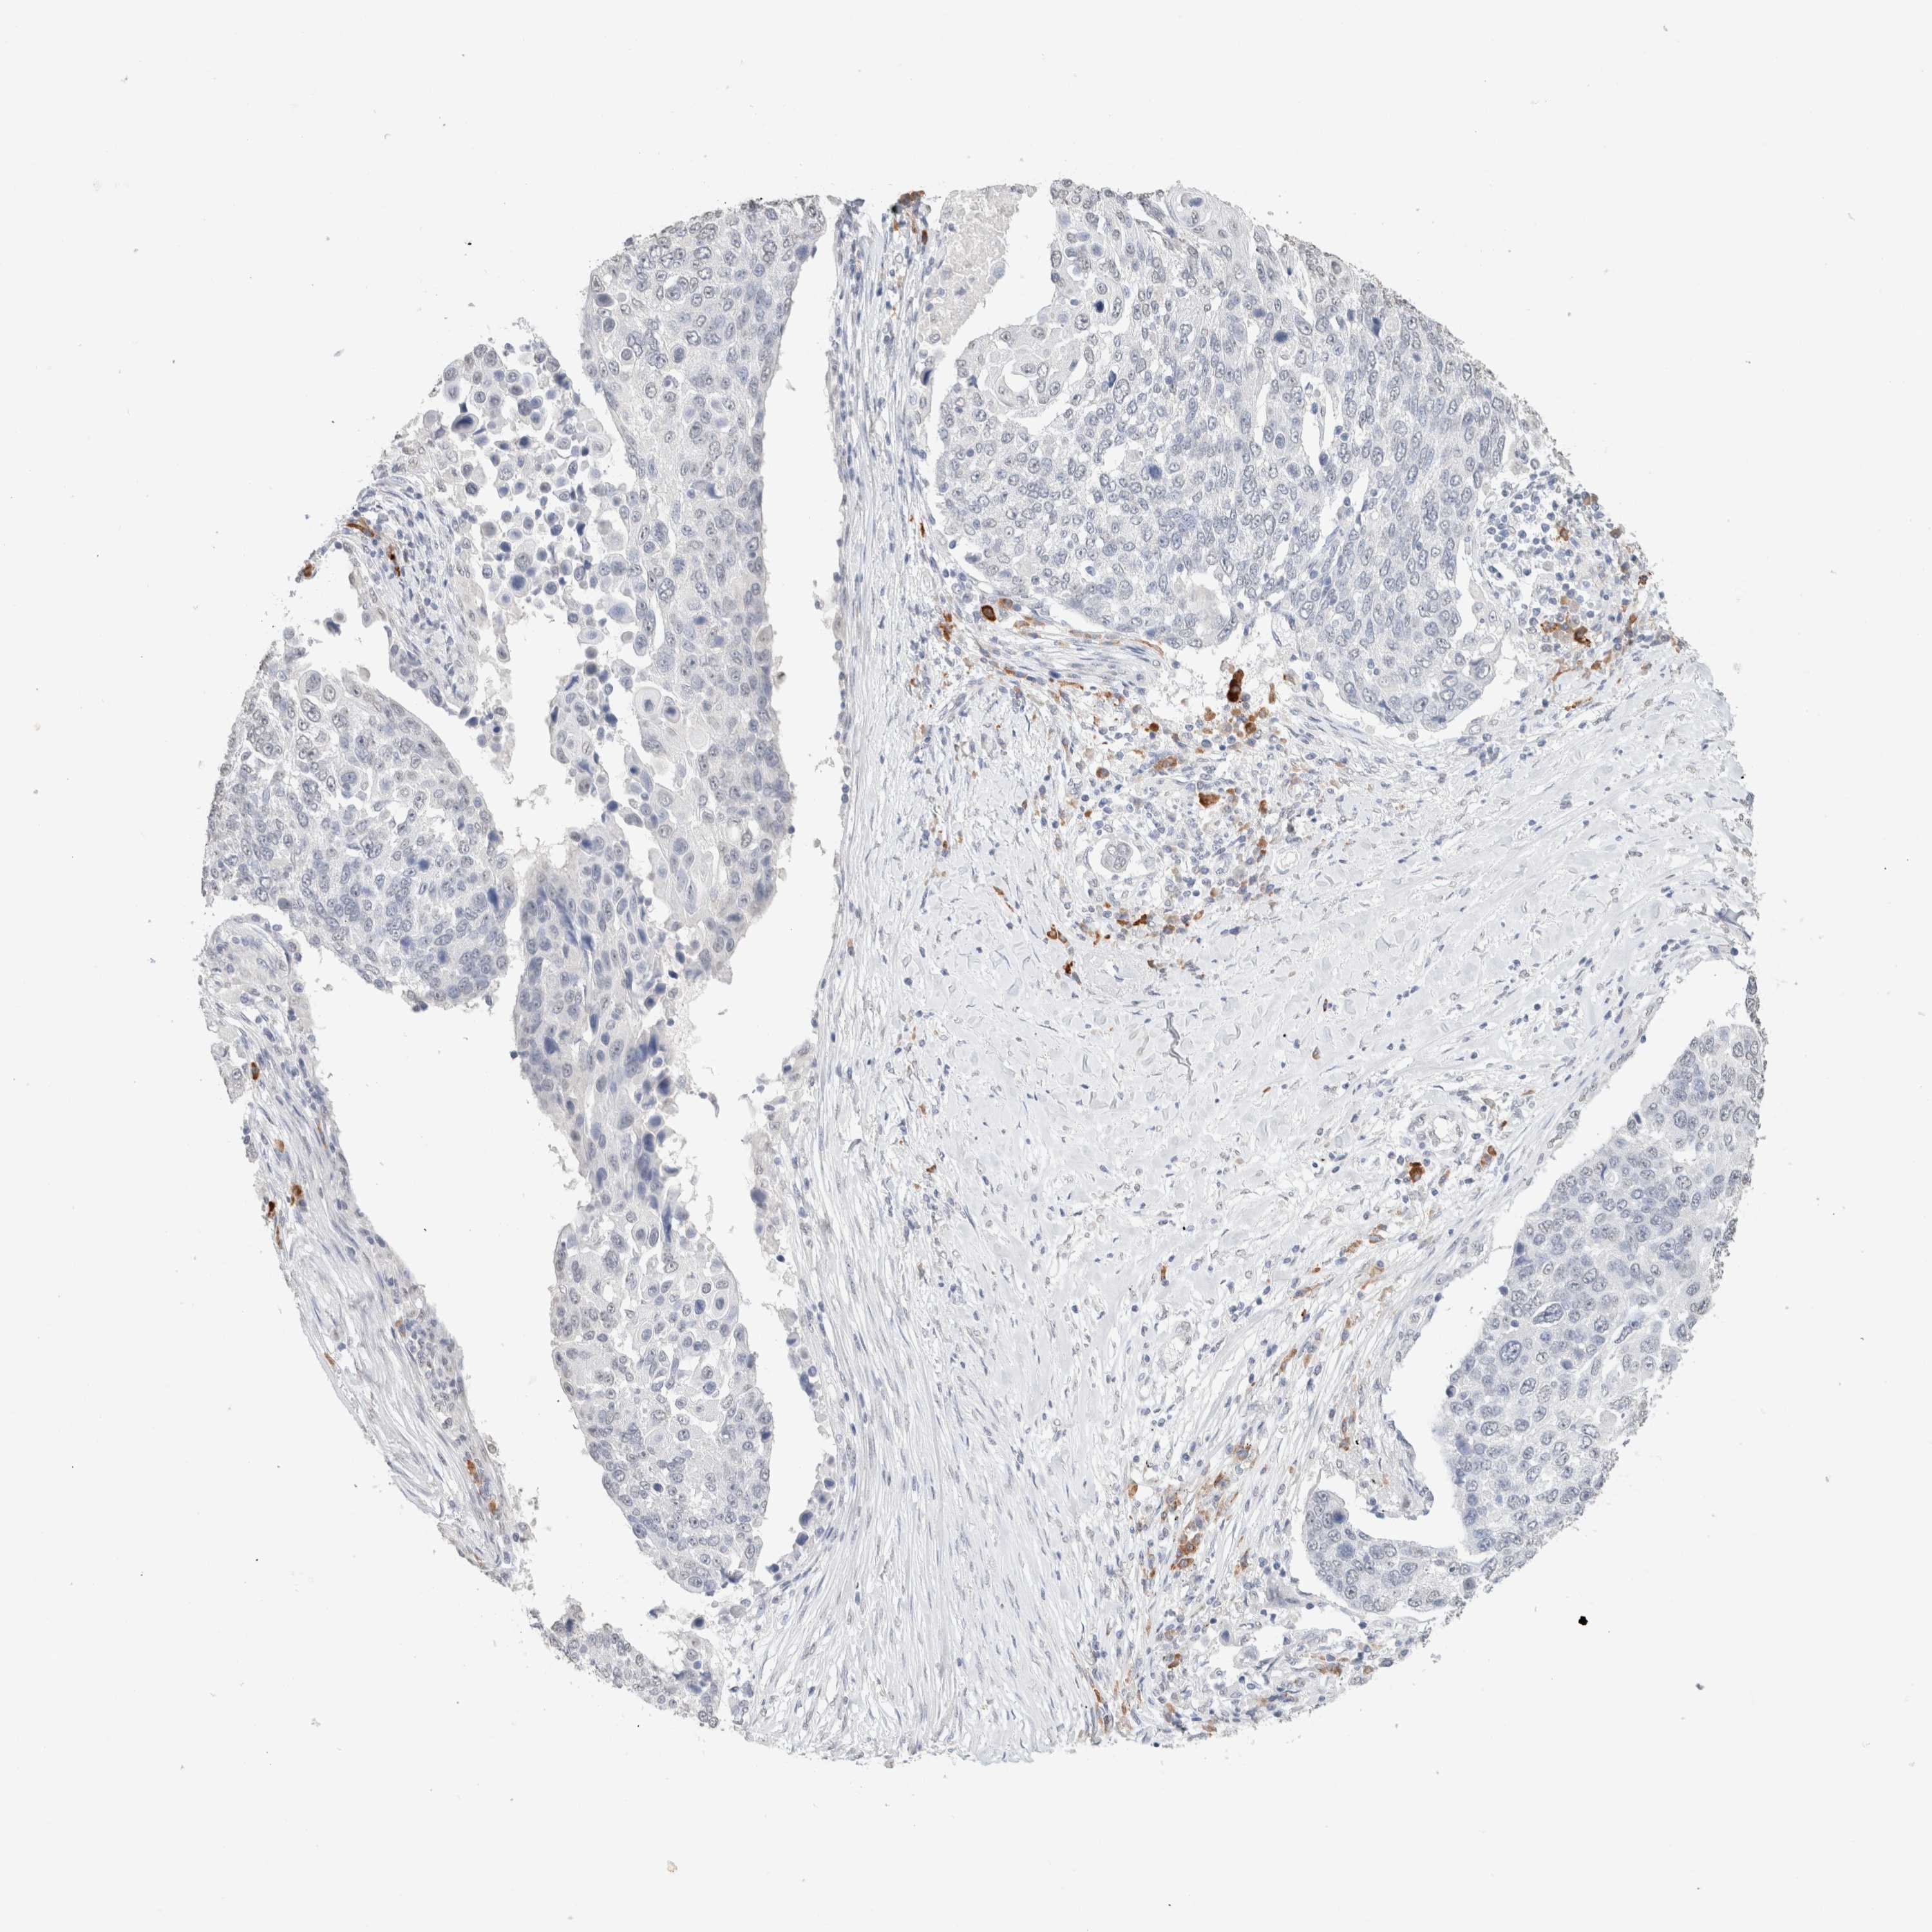

LUNG ADENOCARCINOMA (TCGA) - Interactive survival scatter ploti

The Survival Scatter plot shows the clinical status (i.e. dead or alive) for all individuals in the patient cohort, based on the same data that underlies the corresponding Kaplan-Meier plots. Patients that are alive at last time for follow-up are shown in blue and patients who have died during the study are shown in red.

The x-axis shows the expression levels (FPKM) of the investigated gene in the tumor tissue at the time of diagnosis. The y-axis shows the follow-up time after diagnosis (years). Both axes are complimented with kernel density curves demonstrating the data density over the axes. The top density plot shows the expression levels (FPKM) distribution among dead (red) and alive patients (blue). The right density plot shows the data density of the survived years of dead patients with high and low expression levels respectively, stratified using the cutoff indicated by the vertical dashed line through the Survival Scatter plot. This cutoff is automatically defined based on the FPKM cutoff that minimizes the p-score. The cutoff can be changed by dragging the vertical line or by entering a cutoff value in the square labeled "Current cut-off".

Under the Survival Scatter plot the p-score landscape (black curve; left axis) is shown together with dead median separation (red curve; right axis). Dead median separation is the difference in median mRNA expression between patients who have died with high and low expression, respectively. It is calculated as follows: median FPKM expression of dead patients with high expression - median FPKM expression of dead patients with low expression. This is intended to aid the user in visually exploring custom cutoffs and the associated p-scores and dead median separation.

Individual patient data is displayed and can be filtered by clicking on one or more of the category buttons on the top of the page. Categories describing expression level and patient information include: high, low, alive, dead, female, male and tumor stages. The scale of the x-axis can be toggled between linear and log-scale by clicking on the "x log" button. Mouse-over function shows TCGA ID, patient information and mRNA expression (FPKM) for each patient.

& Survival analysisi

Kaplan-Meier plots summarize results from analysis of correlation between mRNA expression level and patient survival. Patients were divided based on level of expression into one of the two groups "low" (under cut off) or "high" (over cut off). X-axis shows time for survival (years) and y-axis shows the probability of survival, where 1.0 corresponds to 100 percent.

CD80 is not prognostic in Lung Adenocarcinoma (TCGA)

Best expression cut offi

Based on the FPKM value of each gene, patients were classified into two groups and association between prognosis (survival) and gene expression (FPKM) was examined. The best expression cut-off refers the FPKM value that yields maximal difference with regard to survival between the two groups at the lowest log-rank P-value. Best expression cut-off was selected based on survival analysis .

When clicking on this number, the vertical dashed line indicating cut-off, the interactive survival plot, and the Kaplan-Meier curve will be adjusted to show results based on the best expression cut-off.

: 1.59

Median expressioni

Median expression refers to the median FPKM value calculated based on the gene expression (FPKM) data from all patients in this dataset. When clicking on this number, the vertical dashed line indicating cut-off, the interactive survival plot, and the Kaplan-Meier curve will be adjusted to show results based on the median expression.

: N/A

Median follow up timei

Median follow up time refers to the median time (years) after diagnosis with this type of cancer, based on clinical data from all patients in this dataset.

P scorei

Log-rank P value for Kaplan-Meier plot showing results from analysis of correlation between mRNA expression level and patient survival.

N/A

5-year survival highi

5-year survival for patients with higher expression than the expression cutoff.

For melanoma and glioma, 3-year survival is shown.

5-year survival lowi

5-year survival for patients with lower expression than the expression cutoff.

TCGA RNA samplesi

RNA-seq data is reported as average FPKM (number Fragments Per Kilobase of exon per Million reads), generated by the The Cancer Genome Atlas (TCGA) .

Normal distribution across the dataset is visualized with box plots, shown as median and 25th and 75th percentiles. Points are displayed as outliers if they are above or below 1.5 times the interquartile range. FPKM values of the individual samples are presented next to the box plot.

Average pTPM 1.5

Number of samples 497